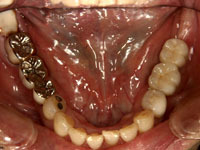

インプラント症例集 失ってから、6年歯がありません。失ってから、6年だそうです。インプラントで歯ができます。 術前 術後 By TDC管理 | 2013年4月30日 | インプラント 治療例 |← 別な患者様の御紹介で当院に来られました。笑顔の写真もアップする予定です。メール配信 予約日前日にメールでお知らせを準備しました。スタッフ、受付さんにお尋ねください →